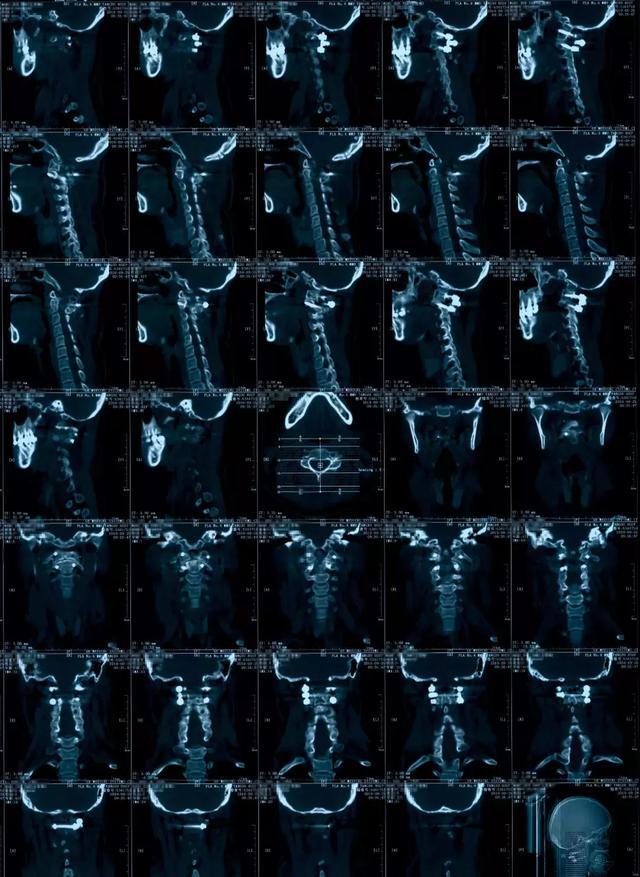

病例分享:寰枢椎融合,椎弓根钉内固定术治疗复杂寰枢椎复合骨折一例

图片尺寸1999x2665

最近完成的一例寰枢关节脱位

图片尺寸1200x1600